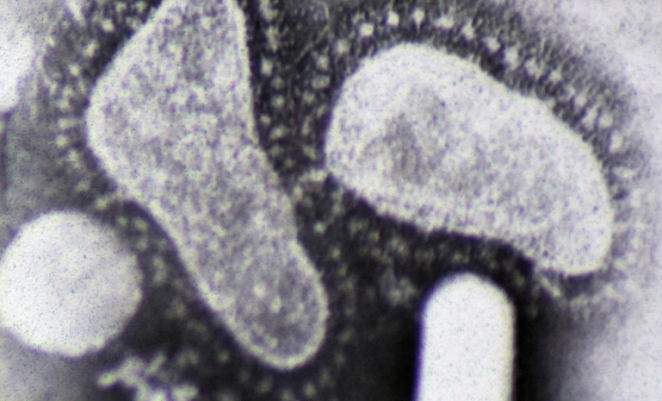

Электронная микрография двух короновирусов / Фото: Dr Graham Beards via Wikimedia

Коронавирус поражает дыхательную систему, желудочно-кишечный тракт или нервную систему, может вызывать бронхит и пневмонию.